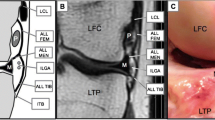

Using the software Materialize Mimics Innovation Suite 22.0 (Materialize GmbH, Gilching, Germany), a 3D model of the lumbar spine of an exemplary patient (patient 8, a 66-year-old male) was created. The location of the IFLs within the IF, as well as the proximity of the surrounding vessels, are depicted in Fig. 3.

Three-dimensional (3D) reconstruction of the lumbar spine using the magnetic resonance imaging (MRI) data from the three-dimensional (3D) constructive interference in steady state (CISS) sequence of a 66-year-old male proband, illustrating the anatomical course of the detected intraforaminal ligaments (black arrow) inside the intervertebral foramina: 1—spinal nerve root, 2—vertebral body, 3—intervertebral disc, 4—ligamenta flava; a shows a semitransparent overview, in a right lateral view; b is a semitransparent lateral close-up of the intervertebral foramina at L2/3; c is a with additional reconstruction of the small vessels

Figure 3 shows the 3D reconstruction with the anatomical course of the explored horizontal lumbar IFLs. CISS sequences from a 66-year-old male proband (patient 8) were used for segmentation. IFLs were detected in all IFs from L1/2 to L4/5 in this specific patient. IFLs were located transversely in the middle zone of the IF and spanned from the inferior articular processes to the intervertebral disc below the spinal nerve. Two transverse IFLs were detected in the IF at L2/3 and L3/4, and one transverse IFL was found in L1/2 and L2/3. The venous plexus surrounding the aforementioned structures of the IF was also exemplarily imaged.

In the present study, we identified the most frequently detected ligamentous structure in the IF as the inferior horizontal ligament (Fig. 3). However, we must note that we did not explicitly classify the detected IFLs in the present study. The IFLs were classified based on their localization from a single subject’s dataset, specifically for the segmentation and illustration seen in Fig. 3.